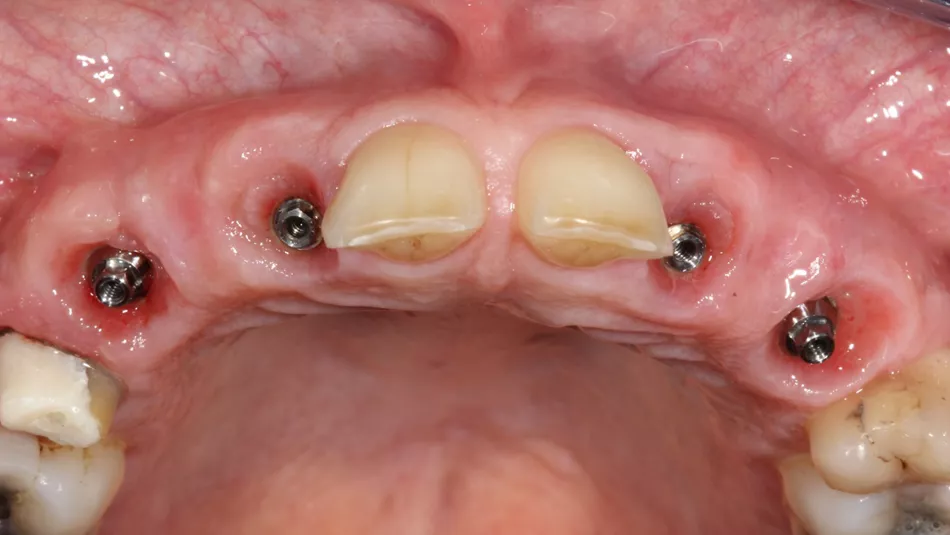

Initial situation

1. The two mesially tipped upper canines and first premolars supported two bridges that had been remade 3 times. Repeated decementation in the upper left quadrant and an infection in 2018 made the patient decide to agree to the proposed implant treatment.

6a-b. Hand-tightening of Ø 4 mm healing screws for the incisors and Ø 5 mm healing screws for the premolars.